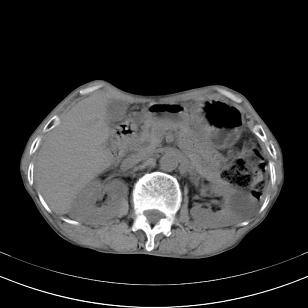

标题: 男,65岁,反复右上腹痛, [打印本页]

标题: 男,65岁,反复右上腹痛,

胃镜提示十二指肠占位